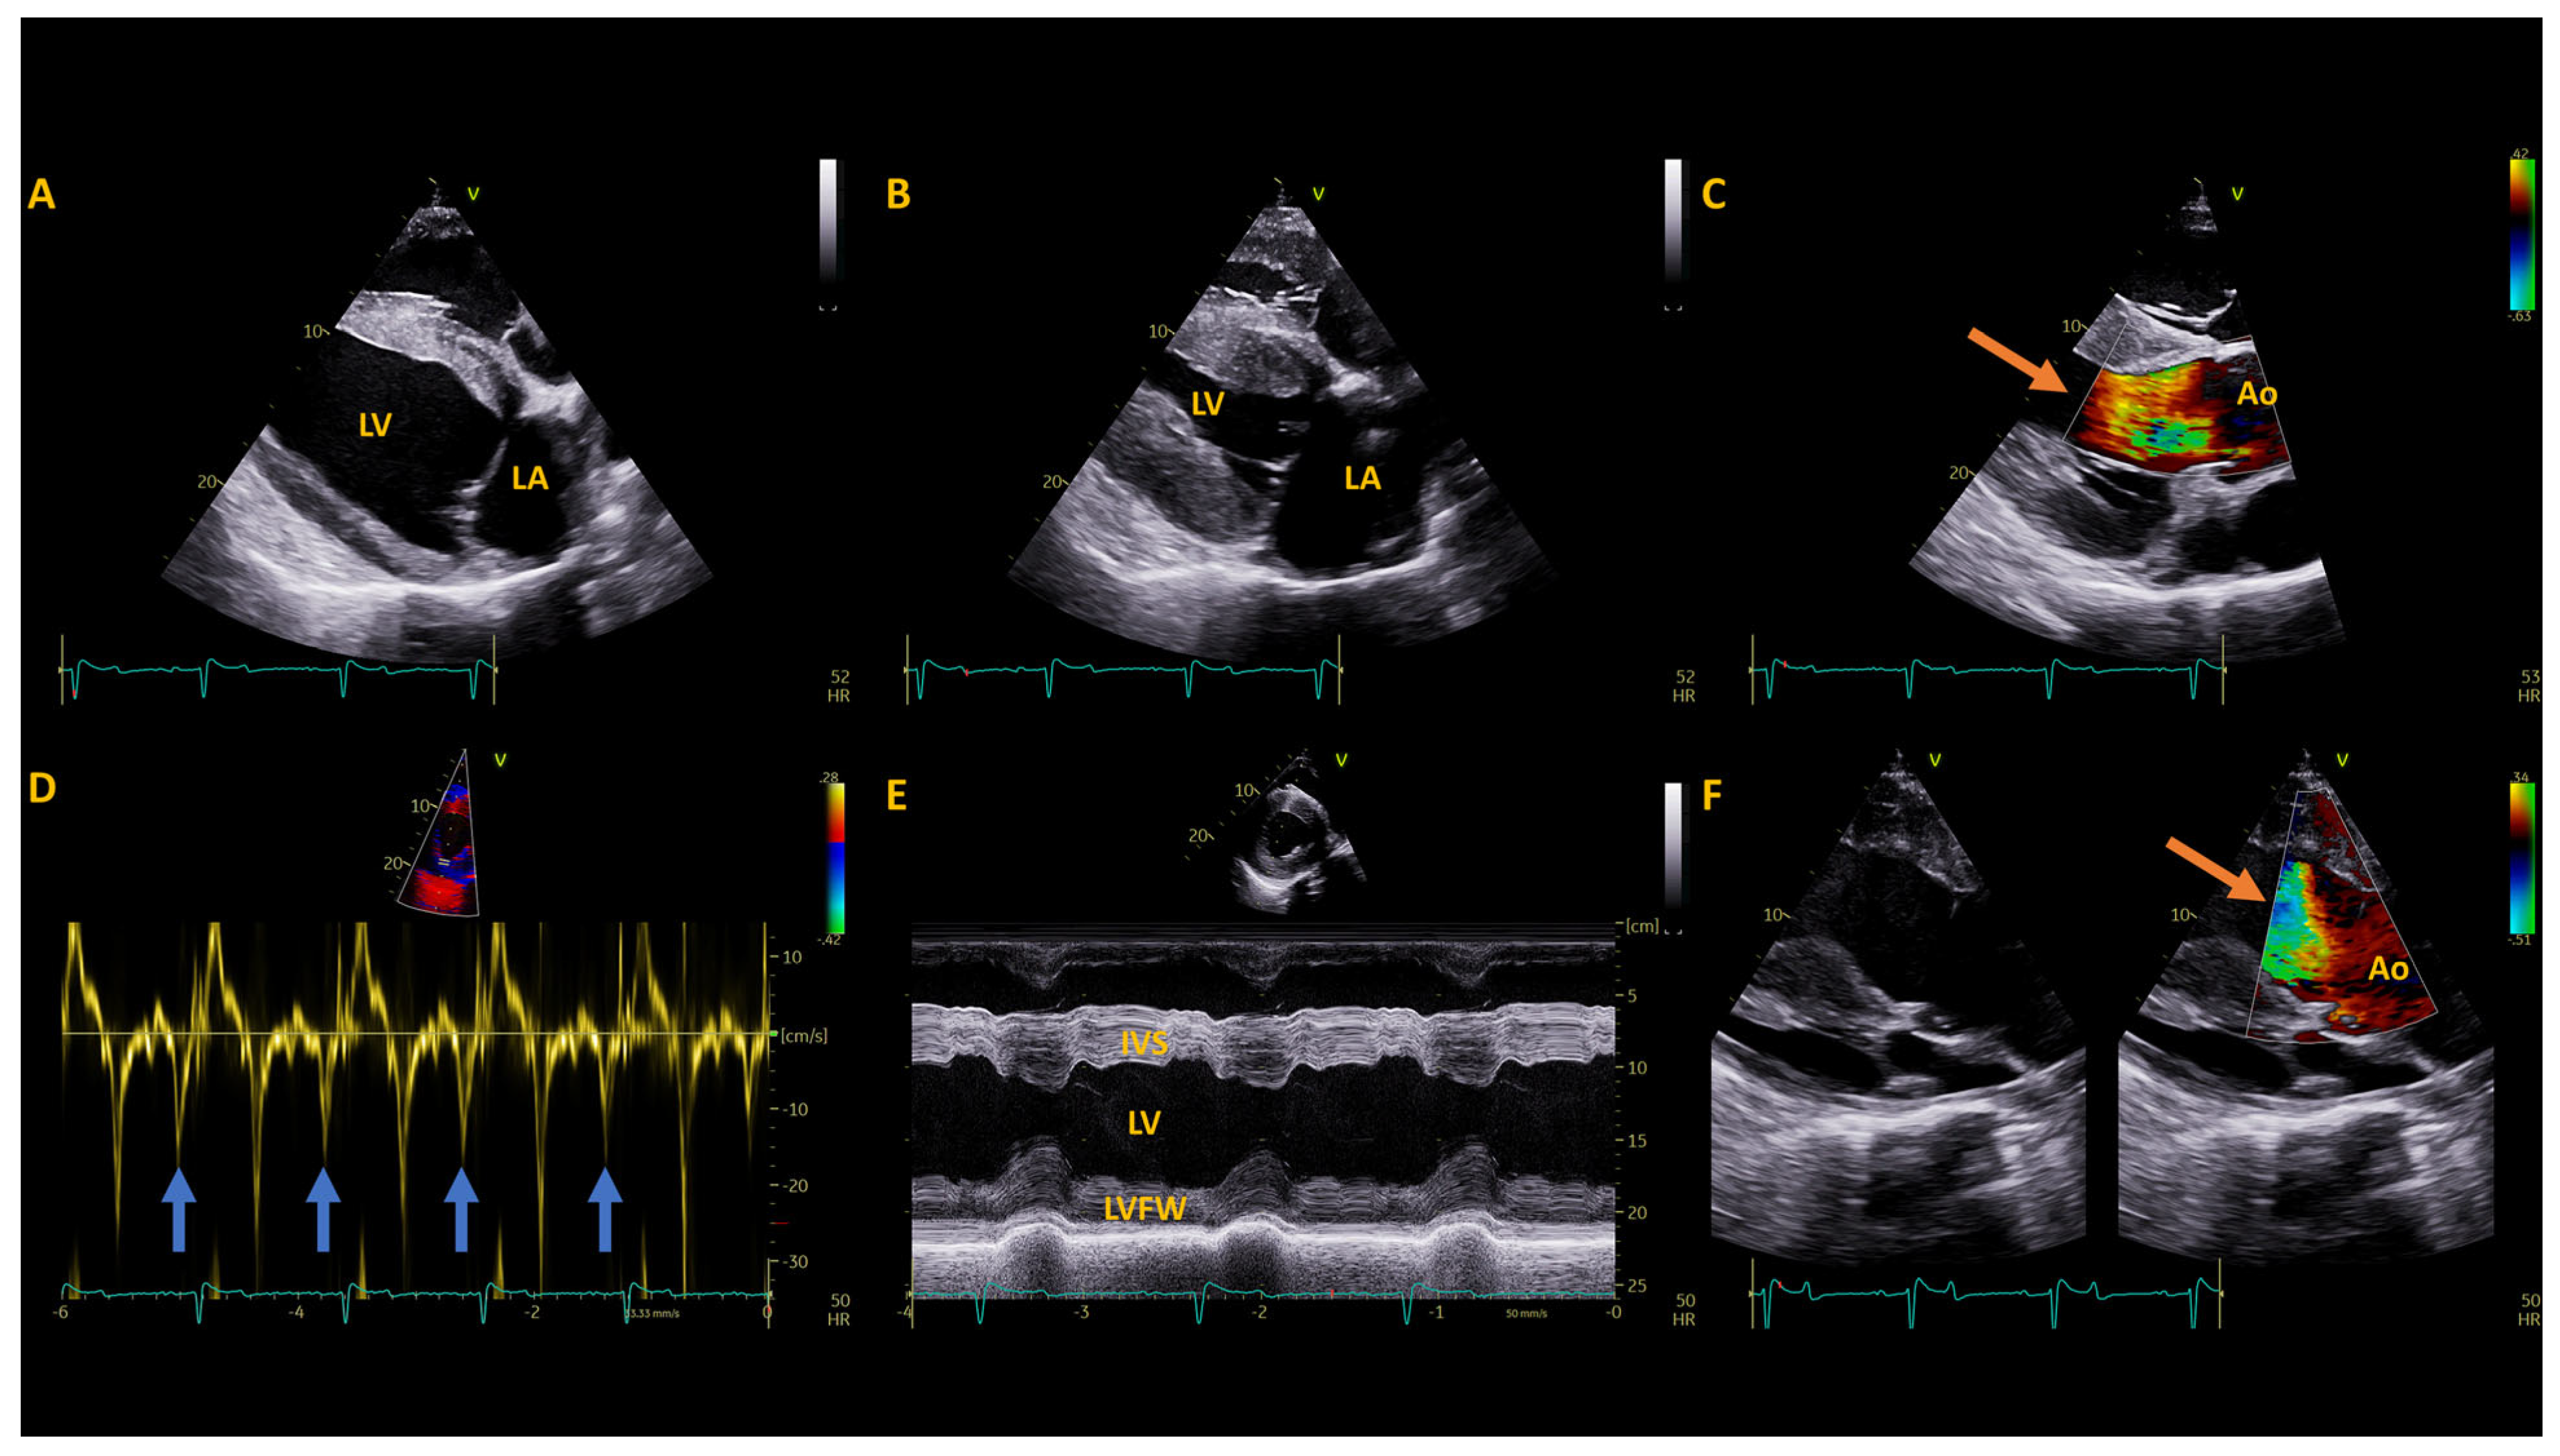

2.2. Pre-Operative Diagnostic Testing

3.1. Post-Operative Diagnostics

4. Discussion